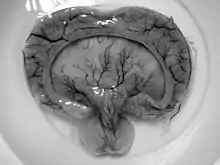

| Gross pathology specimen from a case of alobar holoprosencephaly, a clinical manifestation of Young–Madders syndrome first described as a new condition by doctors Young and Madders in 1987. |